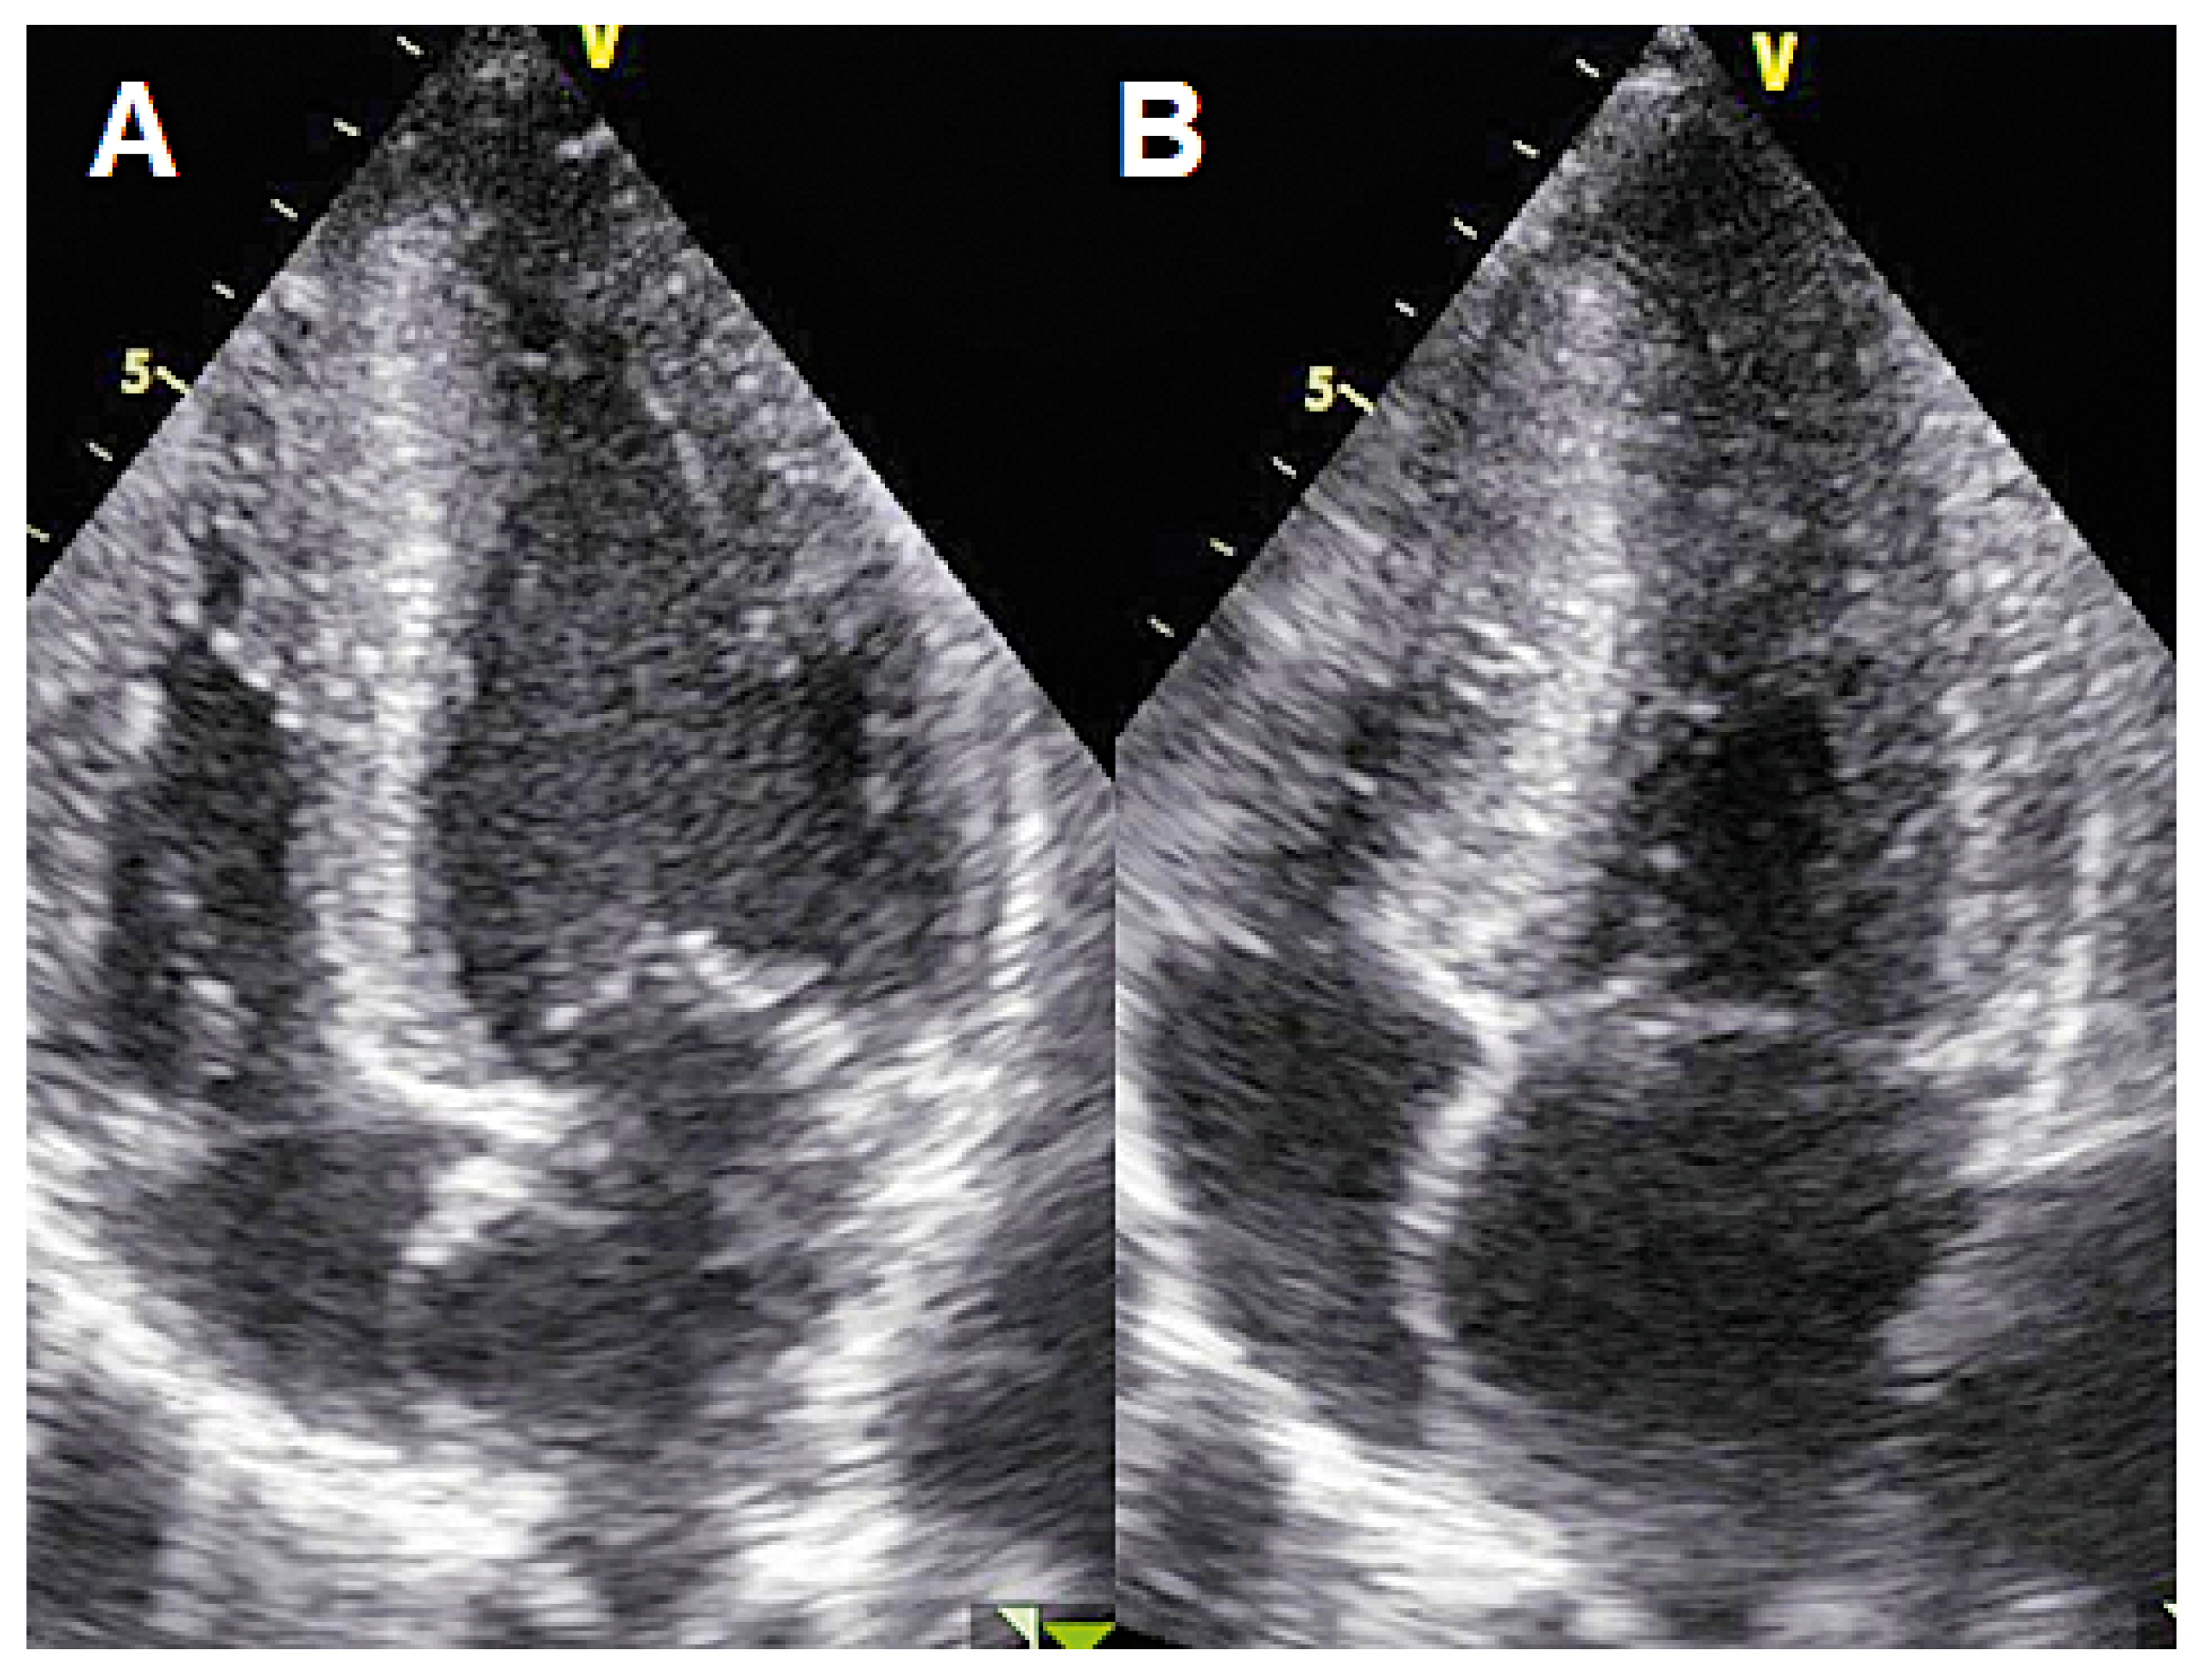

Case 1